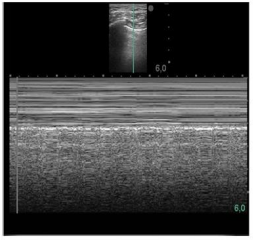

Caso clínico para responder à questão.

Um paciente de 50 anos de idade encontra-se, internado na UTI por conta de choque séptico de foco pulmonar, em ventilação mecânica na modalidade pressão e no modo assisto-controlado. Pela manhã foi submetido a acesso venoso central em veia axilar guiado por ultrassonografia. Ao exame físico, notou-se que o paciente está com hipotensão e taquicardia. A primeira hipótese diagnóstica é pneumotórax e é realizada radiografia com imagem apresentada.